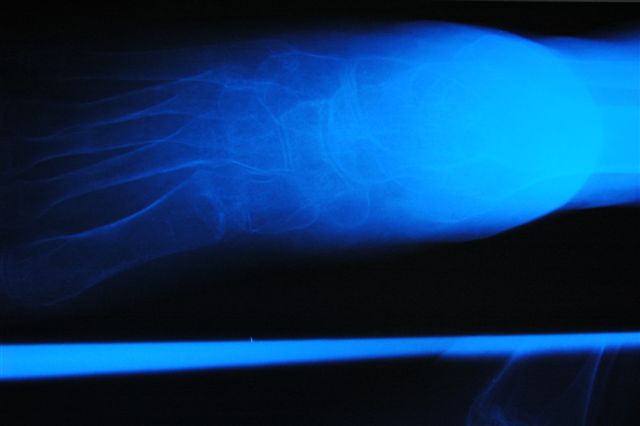

[Ortho] joint distraction, chondrolysis

attached x rays of 15yrs old boy metioned earlier